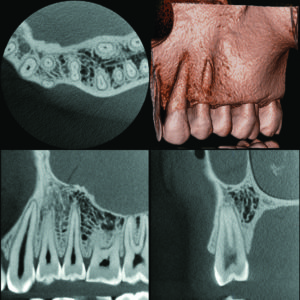

Micro CT

D 40 x H 40 mm